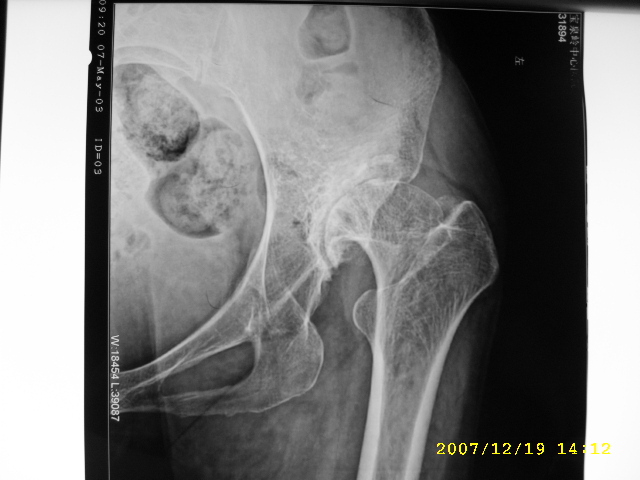

以下是引用逸风在2007-12-19 16:34:00的发言:[br]左侧髋关节间隙变窄,关节面硬化,其下方可见小囊状影,髋臼相对较浅,股骨头未见明显变形,关节面未见塌陷改变;考虑成人髋臼发育不良性骨关节病。